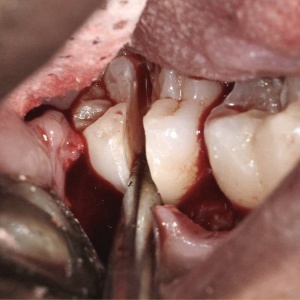

You and your patients will benefit from this practical video! Almost every dentist does some oral surgery, but very few have had significant education in surgical procedures. Karl and Gordon have made a practical, easily understood, step-by-step live video showing necessary concepts, techniques, and instruments needed for oral surgery in your practice. Frequently needed techniques are emphasized, including use of luxators, inter-radicular bone removal, mesial and distal troughing, sectioning roots, and buccal bone removal. Receive many tips on how to make routine surgery faster, easier, and more enjoyable.

- Luxators

- Intra-radicular Bone Removal

- Mesial and/or Distal Troughing

- Patient Surgery